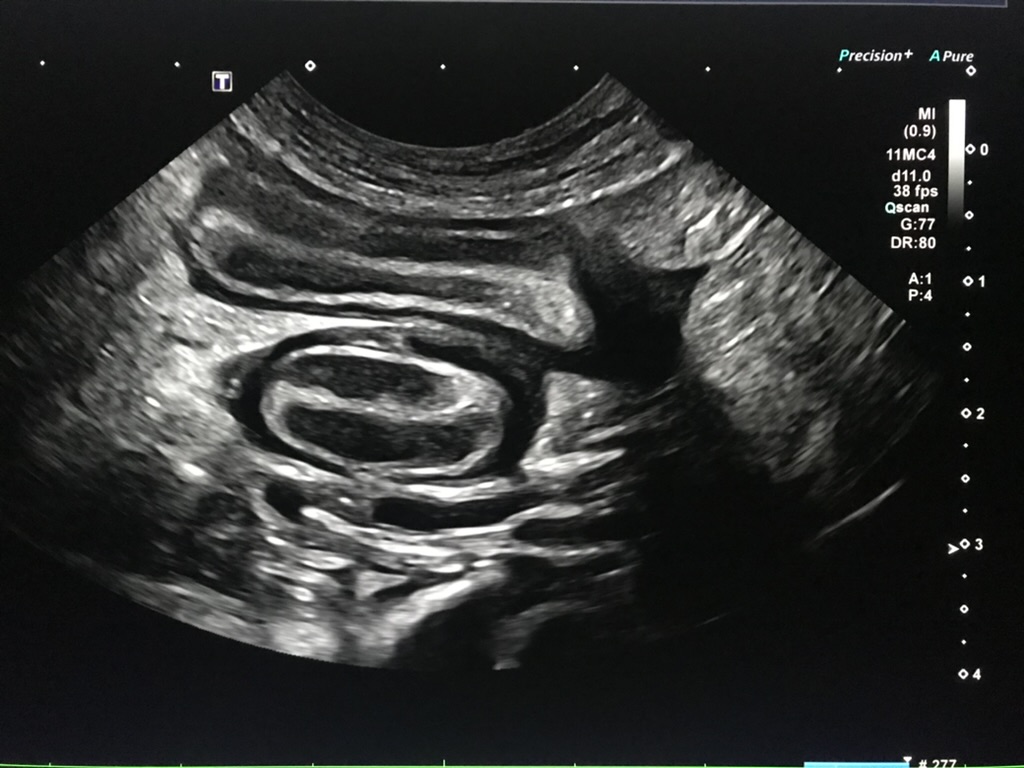

• Best practice technique for Abdominal and Thoracic PoCUS

• Demonstration of the basic abdominal and thoracic PoCUS sites